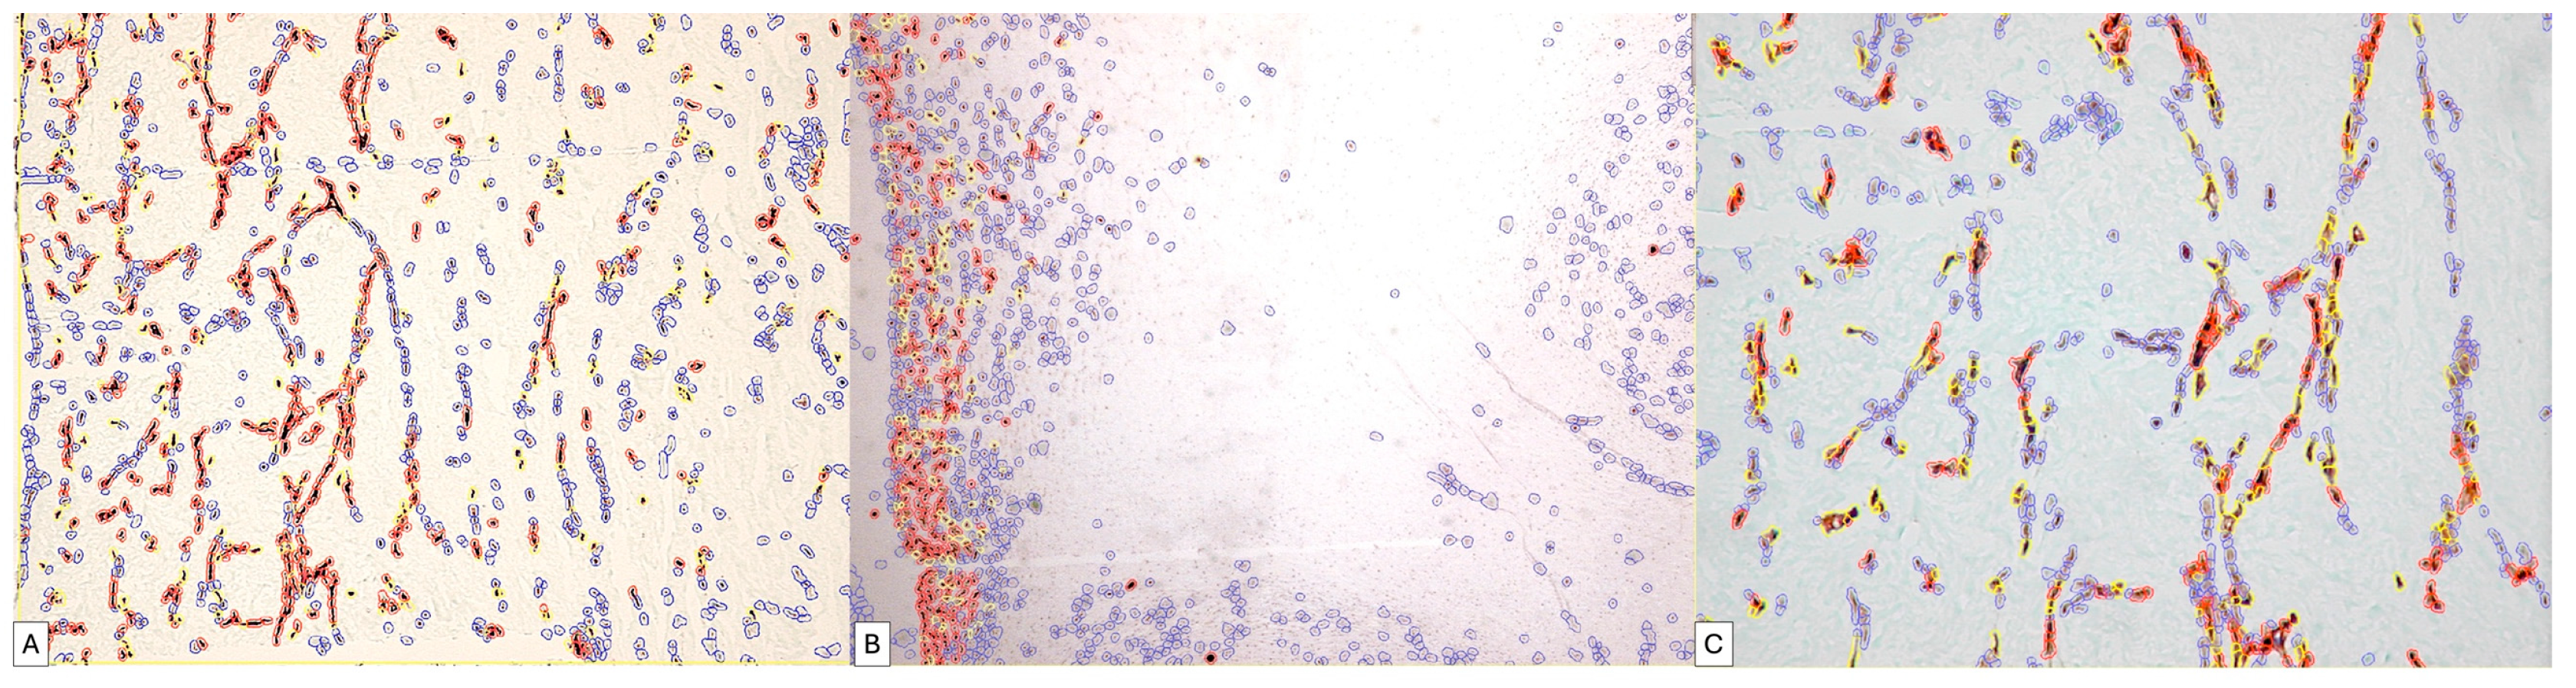

We applied the same image analysis system as the RNAscope automated expression quantification method for the first time (Figure 9).

The use of digital image analysis allowed RNAscope to quantify not only the number of positive punctate signals but also the density and intensity of the punctate signal.

For each case, we identified, on the one hand, the number of positive and negative cells in the selected area but also the proportion of positive signals. Inside the same cell, we could separately identify the number of cells that expressed the PDPN gene by categories of intensity.

The percentage of positive cells varied between 7.98% and 79.48% of the total number of detected cells. Of these, the proportion of positive signals recorded an average score in 40% of cases. The intensity of expression was low, being recorded in 73% of cases as one. Overall, the ALLRED score was five or six in 73% of cases.

Figure 9. The application of the QuPath digital image analysis system for the quantification of mRNA_PDPN expression reclassified the interpretation of positive dotted signals and is based on the intensity of the gene amplification signal. Thus, the accuracy of identifying medium- and low-intensity signals that DIA could detect has increased. It should be noted that the highest morphometric parameters were detected in the trophoblastic cells of the placental nodes (Allred score of 6), while in the mesenchymal-like cells of the chorionic villus axis, the expression was significantly lower.